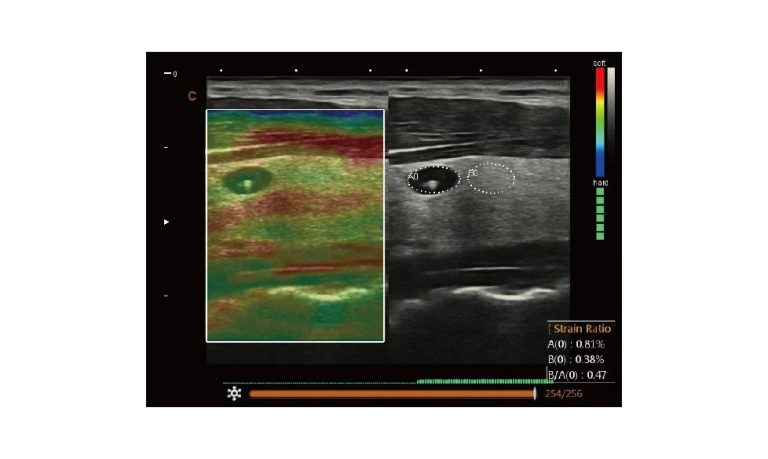

EBIT50/60 VET

All the power you need

The EBit provides all the power you need for today´s challenging clinical environment, yet remain ultra-portable, ultra-affordable. With its cutting-edge imaging technologies, precise and intuitive workflow, ergonomic and eco-friendly design, versatile transducers for all applications from top to toe, we firmly believe the EBit to be the very best portable ultrasound in its class today.